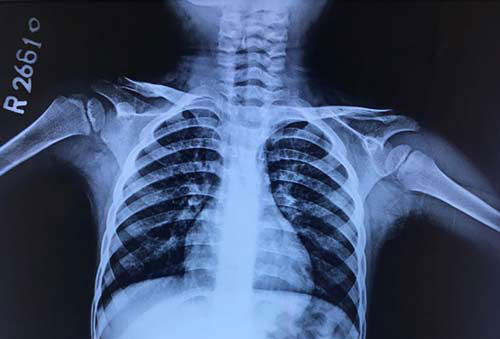

A 4 year old boy came with complaints of dry cough since 15 days and had received antibiotics, nebulization with bronchodilators, inhaled and systemic steroids for the same with no improvement in symptoms. There was no history of fever, nebulization in the past. On examination child had bilateral rhonchi and on enquiry mother gave history of occasional whistling sounds during sleep.

Chest x-ray on admission is shown.

What is your diagnosis?